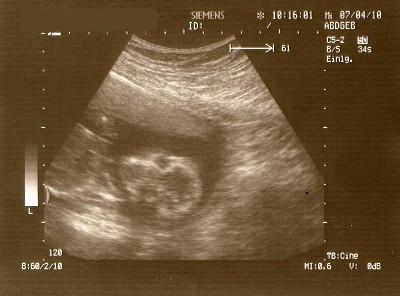

waren heute wieder VU und leider kein outing also es ist aber alles ok das ist doch das wichtigste von der grösse her entspricht es mehr 18+1 obwohl ich heute laut FA 17+2 bin haben dann ein portrait bekommen von dem gesicht voll süss unser kleiner erdenbürger so nannte es unser FA

Bild zu heute beim FA - Forum für September - Mamis